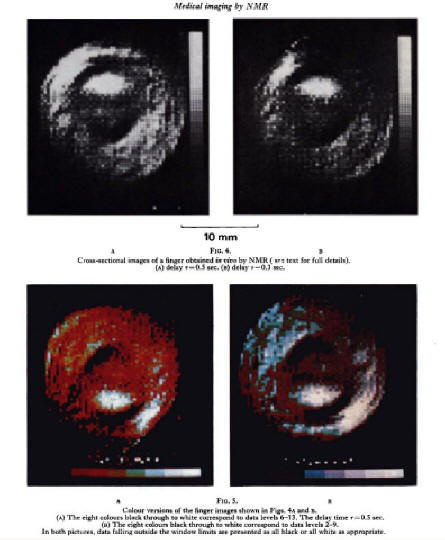

The first MRI scan of a human body part was made by Sir Peter Mansfield (1933–2017), of a cross-section of the finger of his research student Dr Andrew Maudsley. The images were presented at a special meeting of the Medical Research Council in 1976. [Mansfield, Kevles; the finger images were published in P. Mansfield and A. A. Maudsley, 'Medical Imaging by NMR', British Journal of Radiology, 50 (591), 188-194, (1977)]